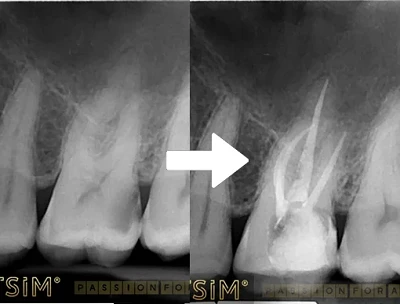

După inserarea implantului dentar, osul din zona intervenției va începe să se regenereze în jurul implantului, ceea ce se numește osteointegrare. Aceasta poate dura între 3 și 4 luni. În toată această perioadă cel mai frecvent se pune pe implant un conformator de gingie (bont de vindecare).